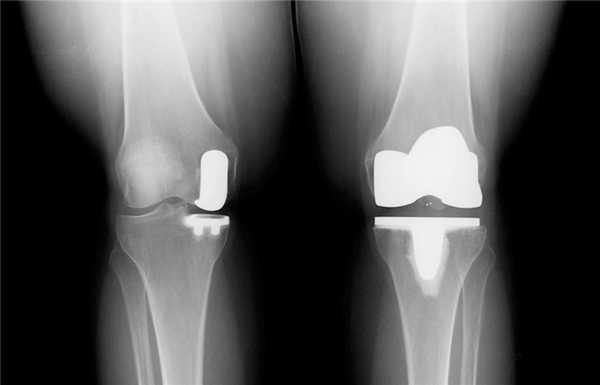

- Старайтесь не набирать избыточный вес после операции. Иначе каждый лишний килограмм будет ускорять изнашивание эндопротеза.

Изношенная платформа берцового компонента коленного эндопротеза.

Несоблюдение мер предосторожности после замены коленного сустава может привести к опасным осложнениям. У человека может случиться вывих эндопротеза или перипротезный перелом. Также возможно асептическое расшатывание имплантата и его преждевременное изнашивание.

Сравнение двух типов операций.